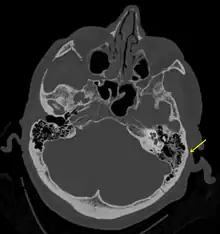

A subtle temporal bone fracture as seen on a CT scan

Temporal bone fractures

Acute injury to the internal carotid artery (carotid dissection, occlusion, pseudoaneurysm formation) may be asymptomatic or result in life-threatening bleeding. They are almost exclusively observed when the carotid canal is fractured, although only a minority of carotid canal fractures result in vascular injury. Involvement of the petrous segment of the carotid canal is associated with a relatively high incidence of carotid injury.[9]